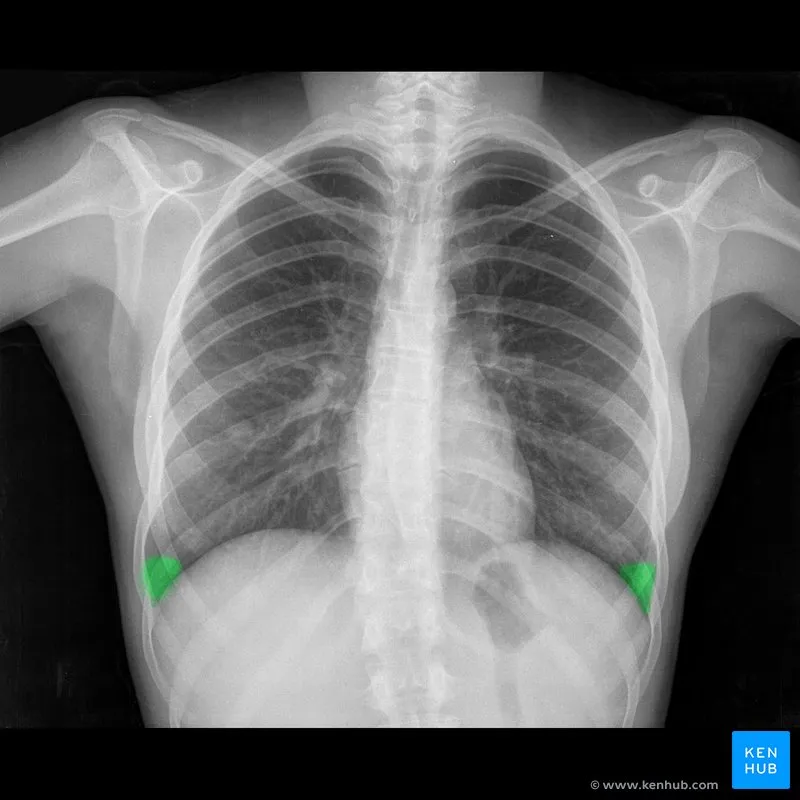

- Pleura & Recesses: Visceral and parietal layers form a potential space.

- Costophrenic angles: Sharp, acute angles formed by the diaphragm and ribs. Blunting suggests pleural effusion.

⭐ Pleural Effusion: On an upright CXR, fluid blunts the costophrenic angle. ~200-300 mL of fluid is required to be visible on a PA view, often forming a meniscus shape.